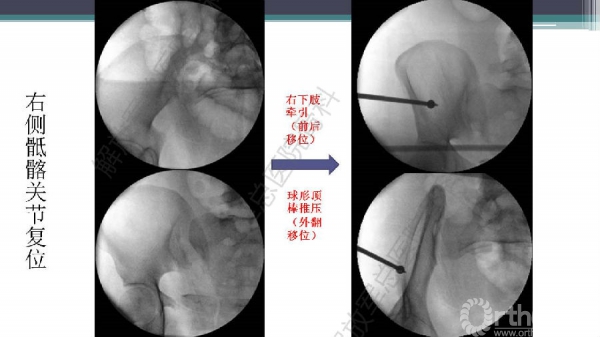

随着建筑和交通运输业的快速发展,合并骨盆、髋臼骨折多发伤、复合伤患者逐年增加,病死率和致残率都非常高。由于多发伤及复合伤、休克等往往不能在急性期对骨盆骨折进行确切复位及内固定,导致陈旧性骨盆骨折畸形愈合,从而产生一系列严重并发症,并且畸形矫正手术难度大、风险高、效果差。因此在抢救复苏后能不能尽早地、小切口甚至不切开、精确复位与固定骨盆骨折,防止陈旧性骨盆畸形愈合形成,成为广大骨科医生的挑战。解放军总医院创伤骨科在骨盆、髋臼骨折微创治疗方面做了一些工作,从微创理论探讨、到手术方法的改进,乃至钢板螺钉、微创复位器械等相继研发,形成了一系列的解决方案和配套内固定产品,为骨盆髋臼骨折的微创治疗奠定了基础。本幻灯则通过一例陈旧骨盆骨折畸形愈合的复杂治疗做引,通过介绍骨盆空间移位方式、透视特点、骨盆随意外架复位系统、复位原理以及1例典型病例的具体实施方案来综合、全面介绍我院微创骨盆髋臼骨折复位、固定新技术。